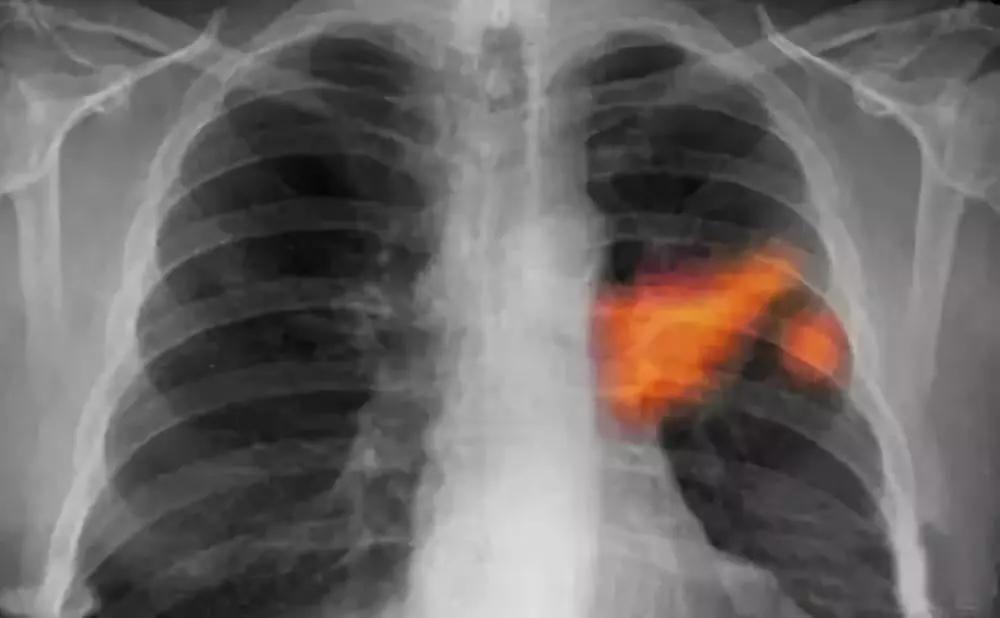

肺癌

多发生在40岁以上男性,长期吸烟者,常有痰中带血,刺激性咳嗽。胸部X线检查肺部有块影或阻塞性肺炎。痰脱落细胞或纤维支气管镜检查可明确诊断。